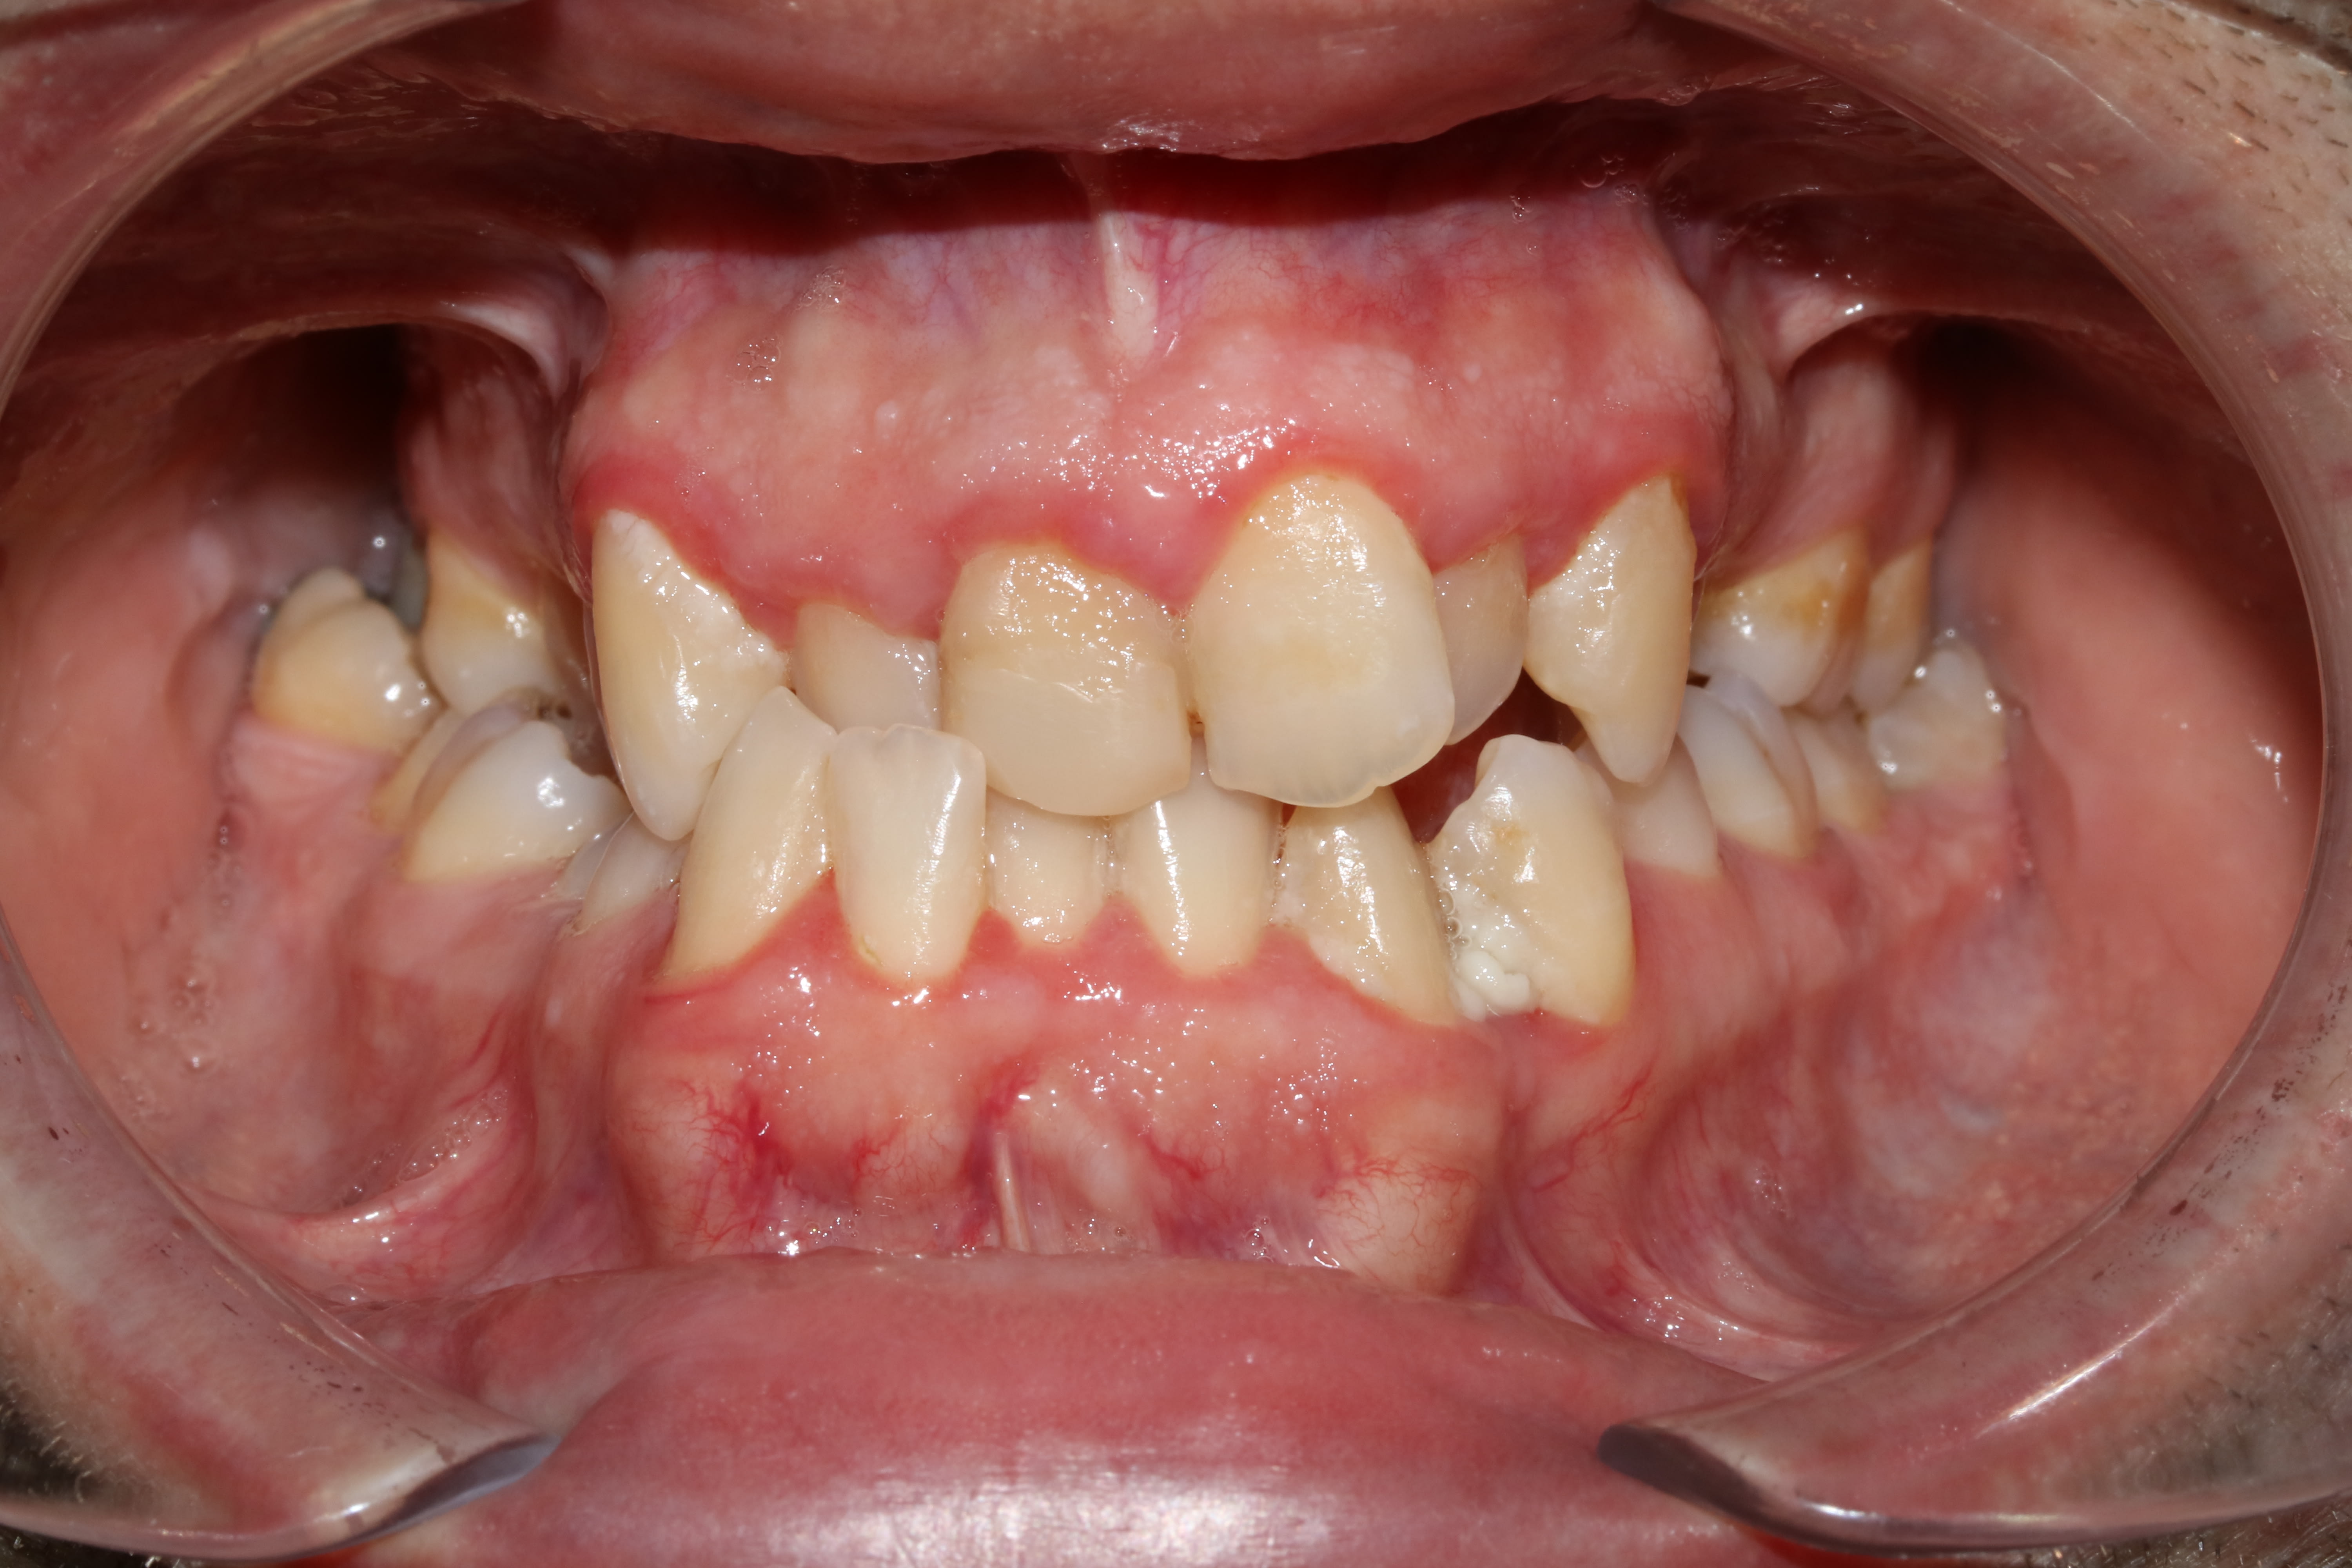

36 ans ...un oublié de l'ortho ...

Arcade md yl4v9v - Eugenol

Arcade mx upxl37 - Eugenol

Droite njf4pn - Eugenol

Face pyrsyz - Eugenol

Gauche snbsdh - Eugenol

sympa, mais au moins il n'a pas 4 CCM soudées en inversé par moitié...